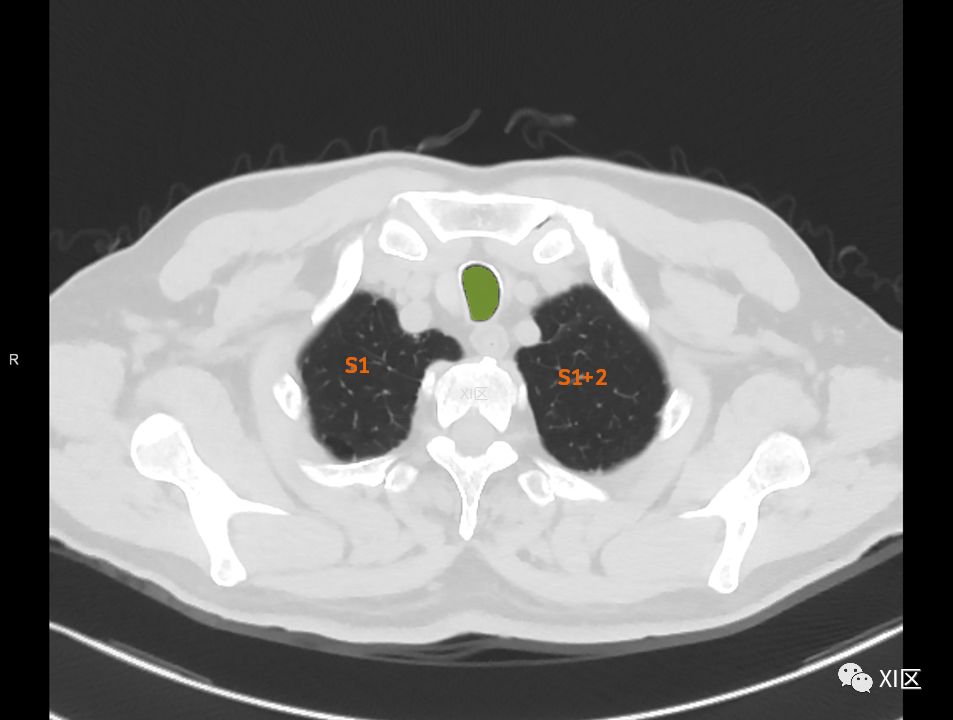

横断位

肺的分段

肺的断层分段示意图

在进行肺的分段时,可以上下观察浏览,沿着相应气管的走形可以更容易准确地进行分段。